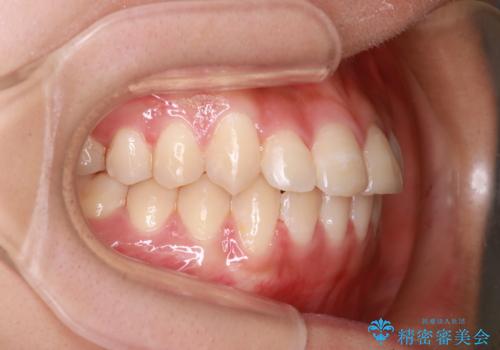

装着時間に不安がある人は、ワイヤー矯正をおすすめしております。短期間で治療でき患者様にも満足していただきました。